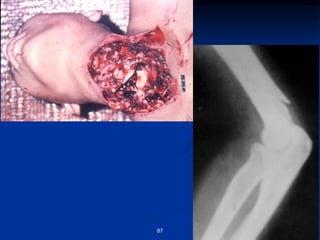

Crush injury

67